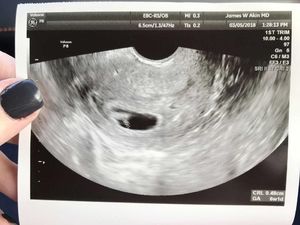

Jessie J mengalami masalah pada rahimnya sehingga ia tidak bisa memiliki anak biologis. Namun itu tak membuatnya patah semangat dan jadikannya lebih kuat.